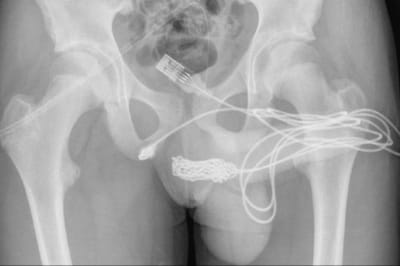

Національний календар щеплень

Фото: МОЗ